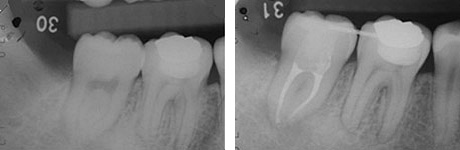

左:移植直後のエックス線写真。

右:移植後1ヶ月。

根管治療直後。歯根が完成している歯を移植歯として用いた場合、歯の神経はつながらないので、このように神経の治療が必要になります。

移植後4ヶ月。

移植歯はコンポジットレジンで修復が行われています。